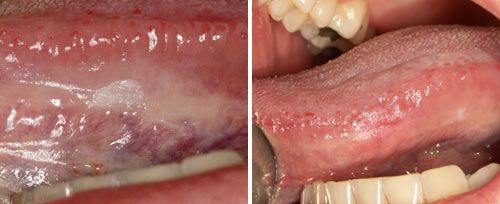

Leukoplakia Treatment

Courtesy of: Assist. Prof. Dragana Gabric, DMD, PhD

Laser source: Er:YAG (2940 nm)